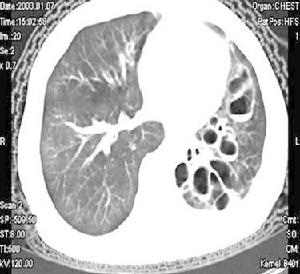

左下肺多發支氣管肺囊腫並感染在成人,多數非感染性囊腫可無症狀,胸片偶然發現,有症狀者,咯血最常見,這幾乎均與囊腫內或周圍感染有關,如囊腫與支氣管的交通呈活瓣機制,可使囊腫迅速增大。

多囊肺

支氣管源性囊腫的分型:依其所在部位分類,分為肺外型和肺內型兩類。依其存在數量分類,分為單髮型、多髮型兩型,後者又分為局部多發(限於肺段或肺葉內)、瀰漫多發(多囊肺)兩個亞型。多囊肺的放射學特徵為多個圓形囊腔如蜂窩狀充滿患肺,有時很像極度充氣的腸袢,故需與膈疝、膈破裂鑑別。